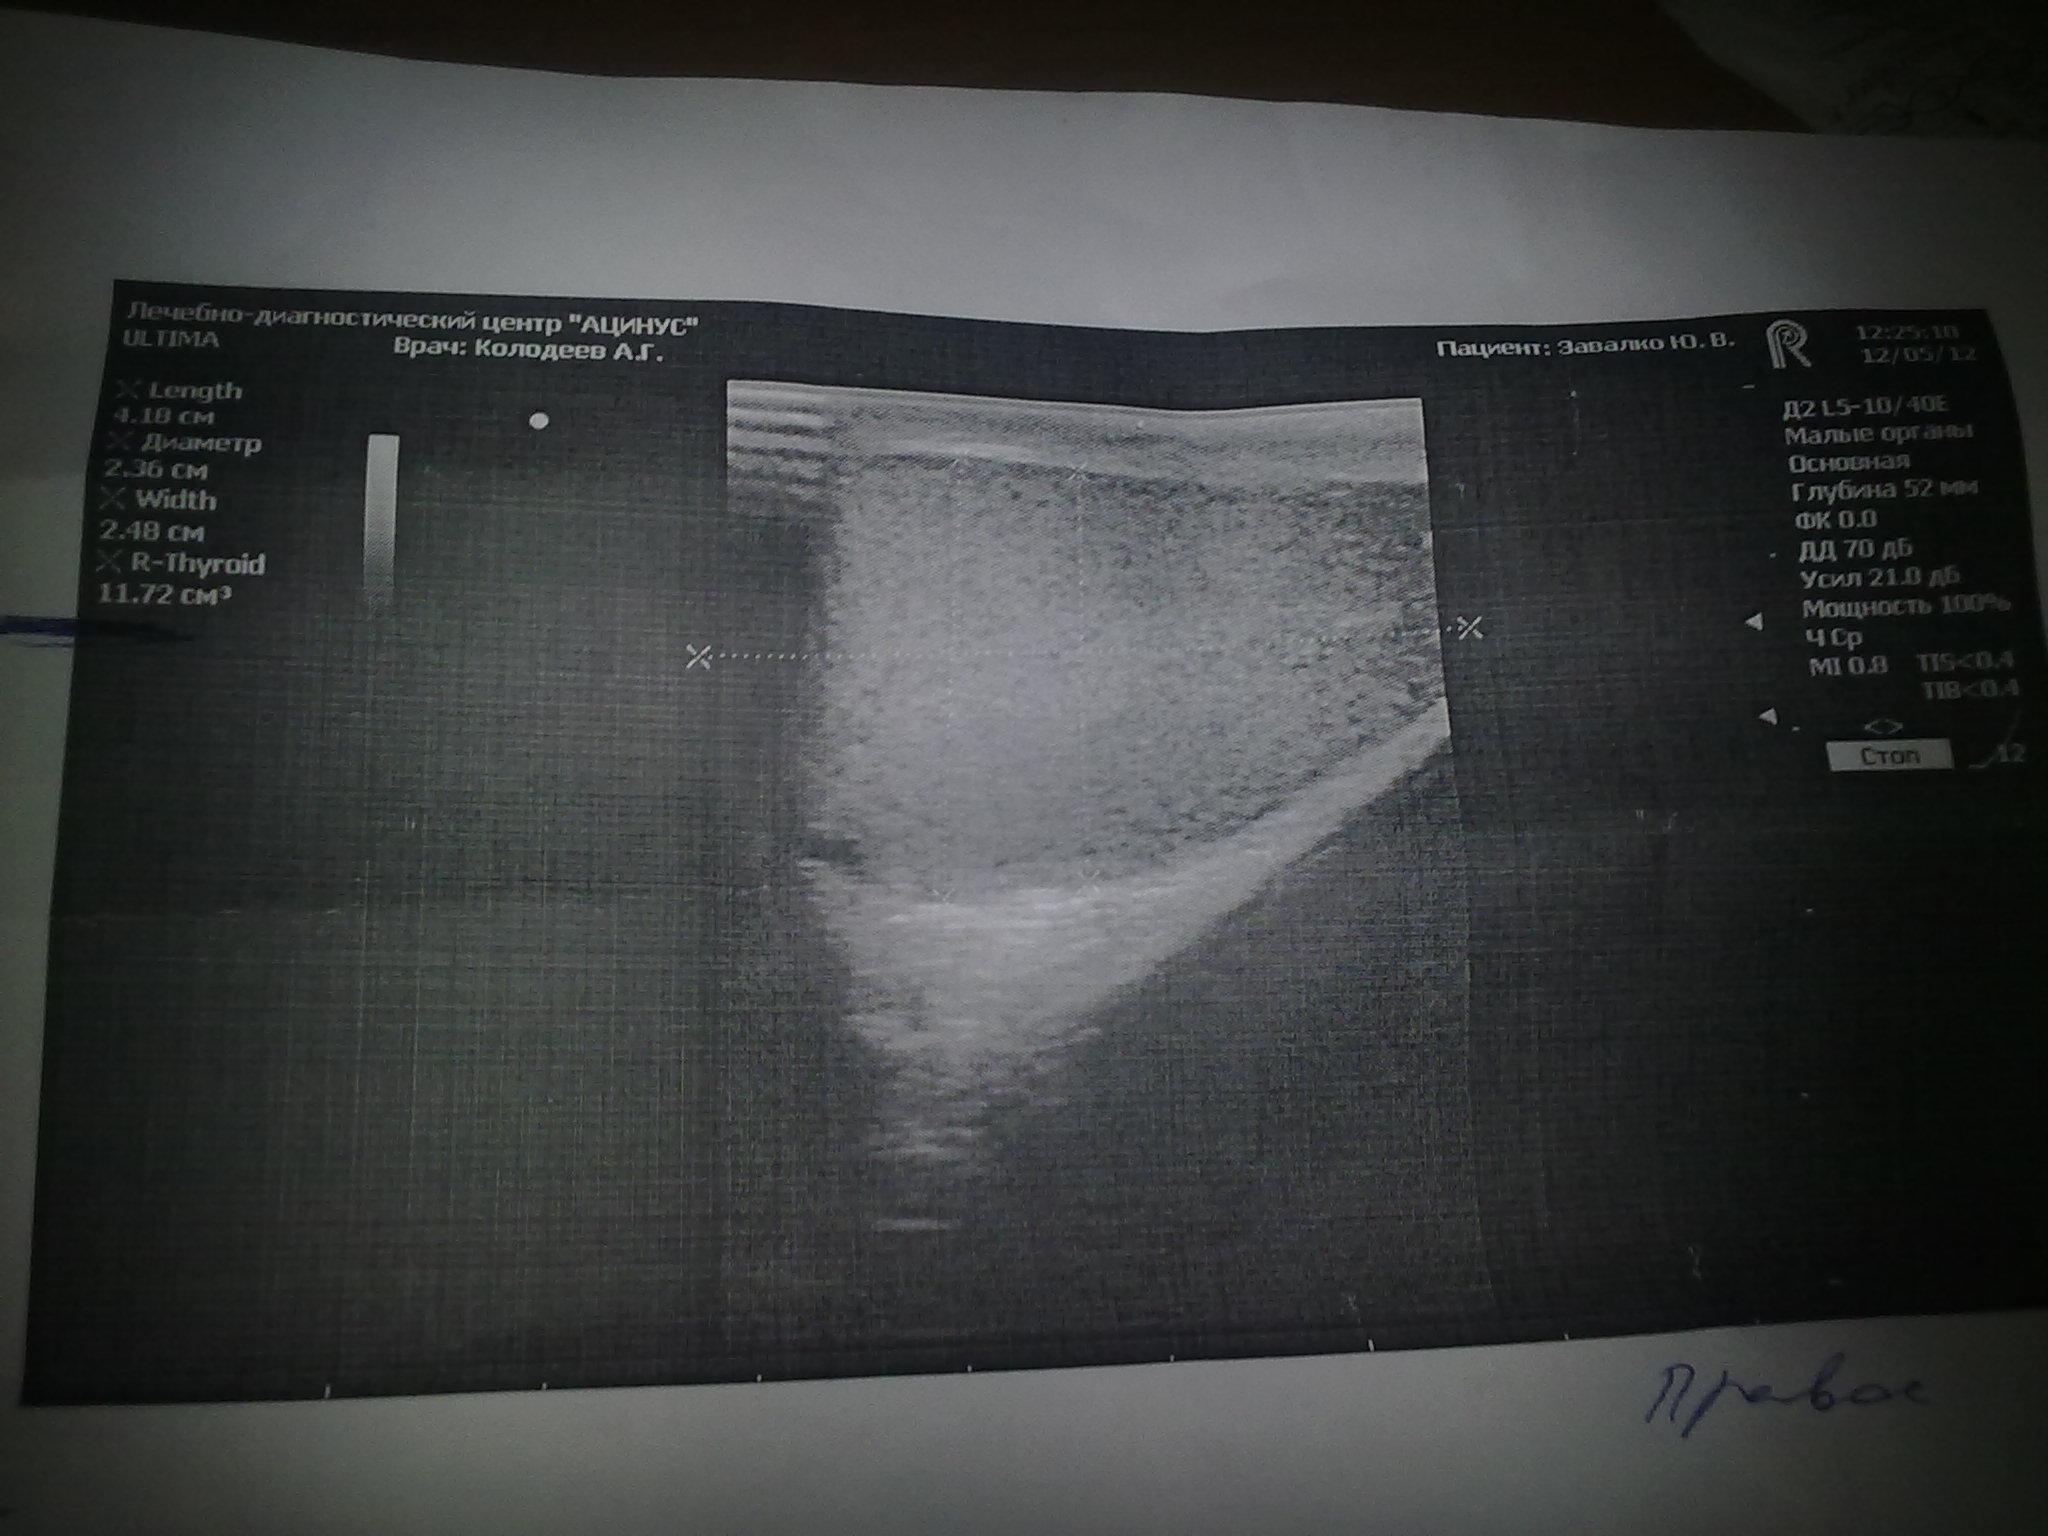

12 мая 2012 - 14:24

Пол:

Мужской

Возраст:

38 года

здравствуйте я сделал узи мошонки и сказали всё в норме. Так с чего у меня явно уменьшились яички особенно левое?

Нечитаемый текст.